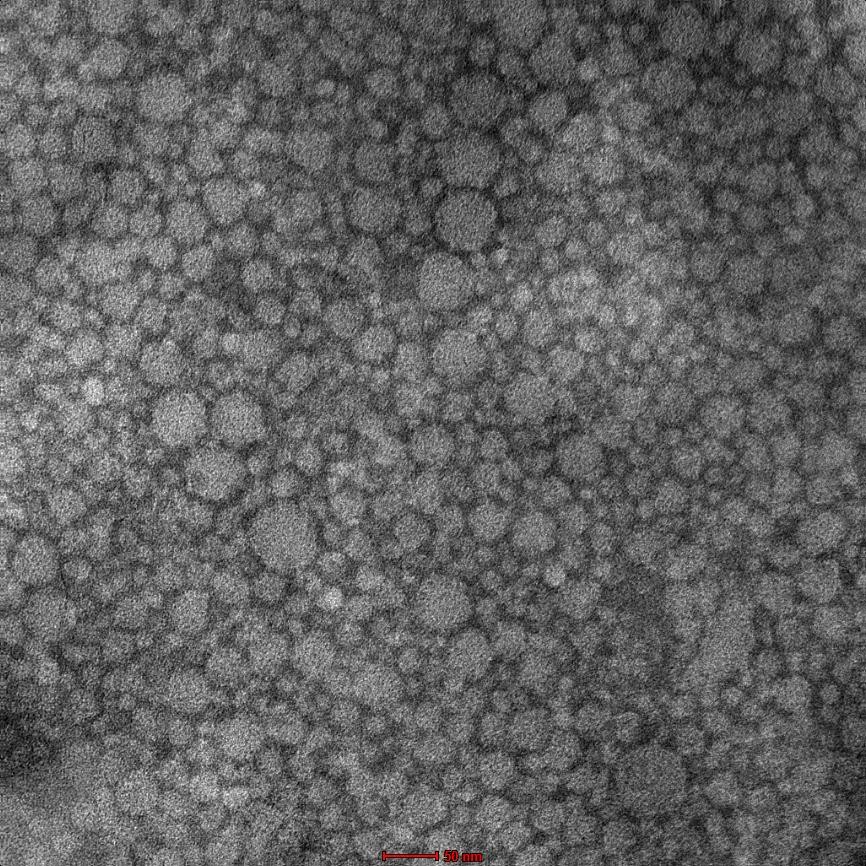

High-resolution transmission electron microscopy (HR-TEM)

Samples were negatively stained with 2% phosphotungstic acid and imaged. The instrument (JEOL JEM-2100, Japan) was operated at 120KV [19, 20].

The desirability optimized formulation (GMS 9.21%, Capmul MCM 2.17%, Transcutol 2.17%) was prepared following the procedure outlined previously. The optimized formulation of NLC provided PS of 142.3 nm and EE of 90.21%. These results are in agreement with another study where NLCs of quercetin, along with another phytconstitutent showed low particle size and high entrapment efficiency [33]. HR‑TEM conducted on the optimized formulation showed spherical NLCs and in close agreement of the particle size obtained by DLS. The optimized batch showed a negative zeta potential of-13.3±2.1 mV and showed drug loading of approximately 1 % (0.9±0.04). Thus, it can be said that the chosen excipients at the levels used could successfully prepare a low particle size stable NLC dispersion with good entrapment efficiency. QbD facilitated efficient optimization and defined a design space for robust manufacture [32, 36].

Fig. 2: HR-TEM of optimized NLC formulation (Magnification 150,000X)